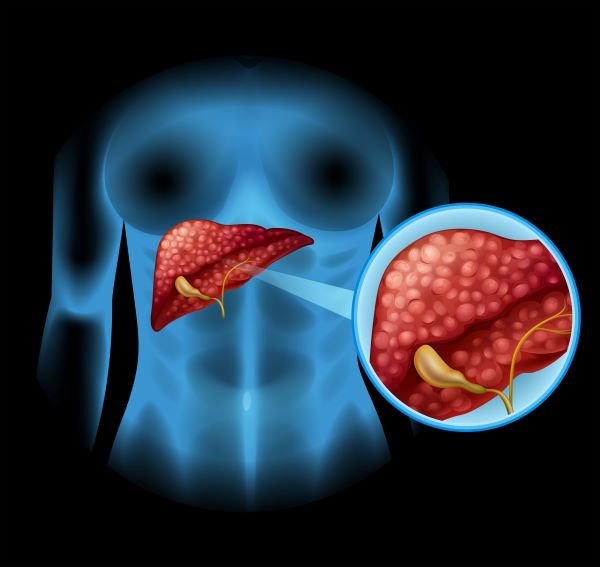

C형간염 간경화로 진행되면 어떻게 달라질까?

단계별 증상으로 미리 알아보는 위험 신호

C형간염이 무서운 이유는 단순히 “간에 염증이 생긴다”는 점 때문이 아닙니다.

치료하지 않고 방치하면 간경화 → 간부전 → 간암이라는 흐름으로

서서히 진행되기 때문입니다.

하지만 이 과정은 하루아침에 일어나지 않습니다.

단계별로 분명한 신호가 존재합니다.

1단계: 만성 C형간염 (초기)

3단계: 간경화 초기 (보상성 간경화)

간이 많이 손상되었지만

아직은 스스로 기능을 유지하고 있는 상태입니다.

- 체중 감소

- 쉽게 멍이 듦

- 잇몸 출혈

- 복부에 핏줄이 도드라져 보임

- 손바닥이 붉어지는 증상

👉 겉보기에는 일상생활 가능

👉 그러나 간암 위험이 급격히 증가하는 시점입니다.

4단계: 비보상성 간경화

이 단계부터는 명확하고 위험한 증상이 나타납니다.

- 복수(배에 물이 참)

- 다리 부종

- 황달

- 의식 저하

- 토혈, 혈변

👉 이 단계에서는

✔ 치료가 어려워지고

✔ 입원 치료가 필요하며

✔ 간 이식까지 고려해야 할 수 있습니다.